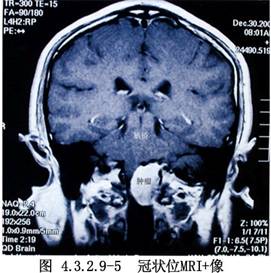

枕骨大孔區的腫瘤以腦膜瘤多見,神經鞘瘤次之,腦膜瘤常發生於枕骨大孔區環竇附近,部位多靠近側面或偏向前或偏向後。其供血主要來源於腫瘤基底的腦膜動脈,也有一部分來自椎動脈與小腦下後動脈分支。腫瘤長大可使第9、10、11、12顱神經受累,同時也可壓迫延髓與上段頸髓,發生球麻痹與錐體束徵等症狀。神經鞘瘤主要來自頸神經根,通過枕骨大孔向上長入顱後窩,尚有舌咽神經瘤與舌下神經瘤(圖4.3.2.9-1~4.3.2.9-5)。

1.術前必須有正確的定位診斷。近年來由於影像檢查技術的進步,CT、MRI、DSA等臨牀應用日益廣泛。對病變的部位及與周圍結構的關係術前應詳加分析,以便選擇合適的手術入路,爭取獲得最好的顯露,儘可能地避開顱內重要結構,增加手術的安全性和爭取良好的效果。